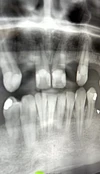

التصوير المقطعي للأسنان